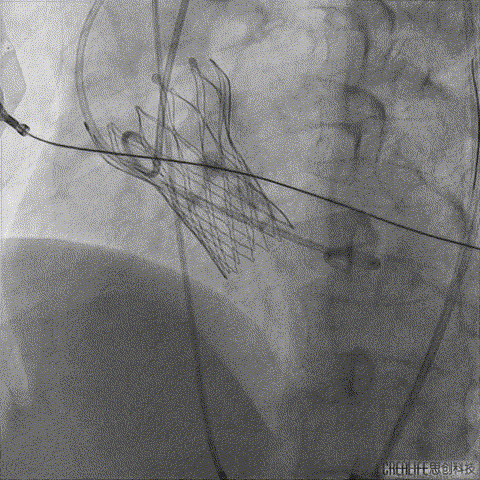

术前CT分析右侧的冠脉风险较高,球囊预扩前右冠开口处预放一个冠脉保护支架,采用18mm球囊预扩,有轻微腰征,无造影剂渗漏;

右侧冠脉保护准备

球囊预扩

TaurusElite输送系统轻松过弓、跨瓣,AV23瓣膜瓣环上约2mm释放;

TaurusElite轻松过弓

瓣膜释放